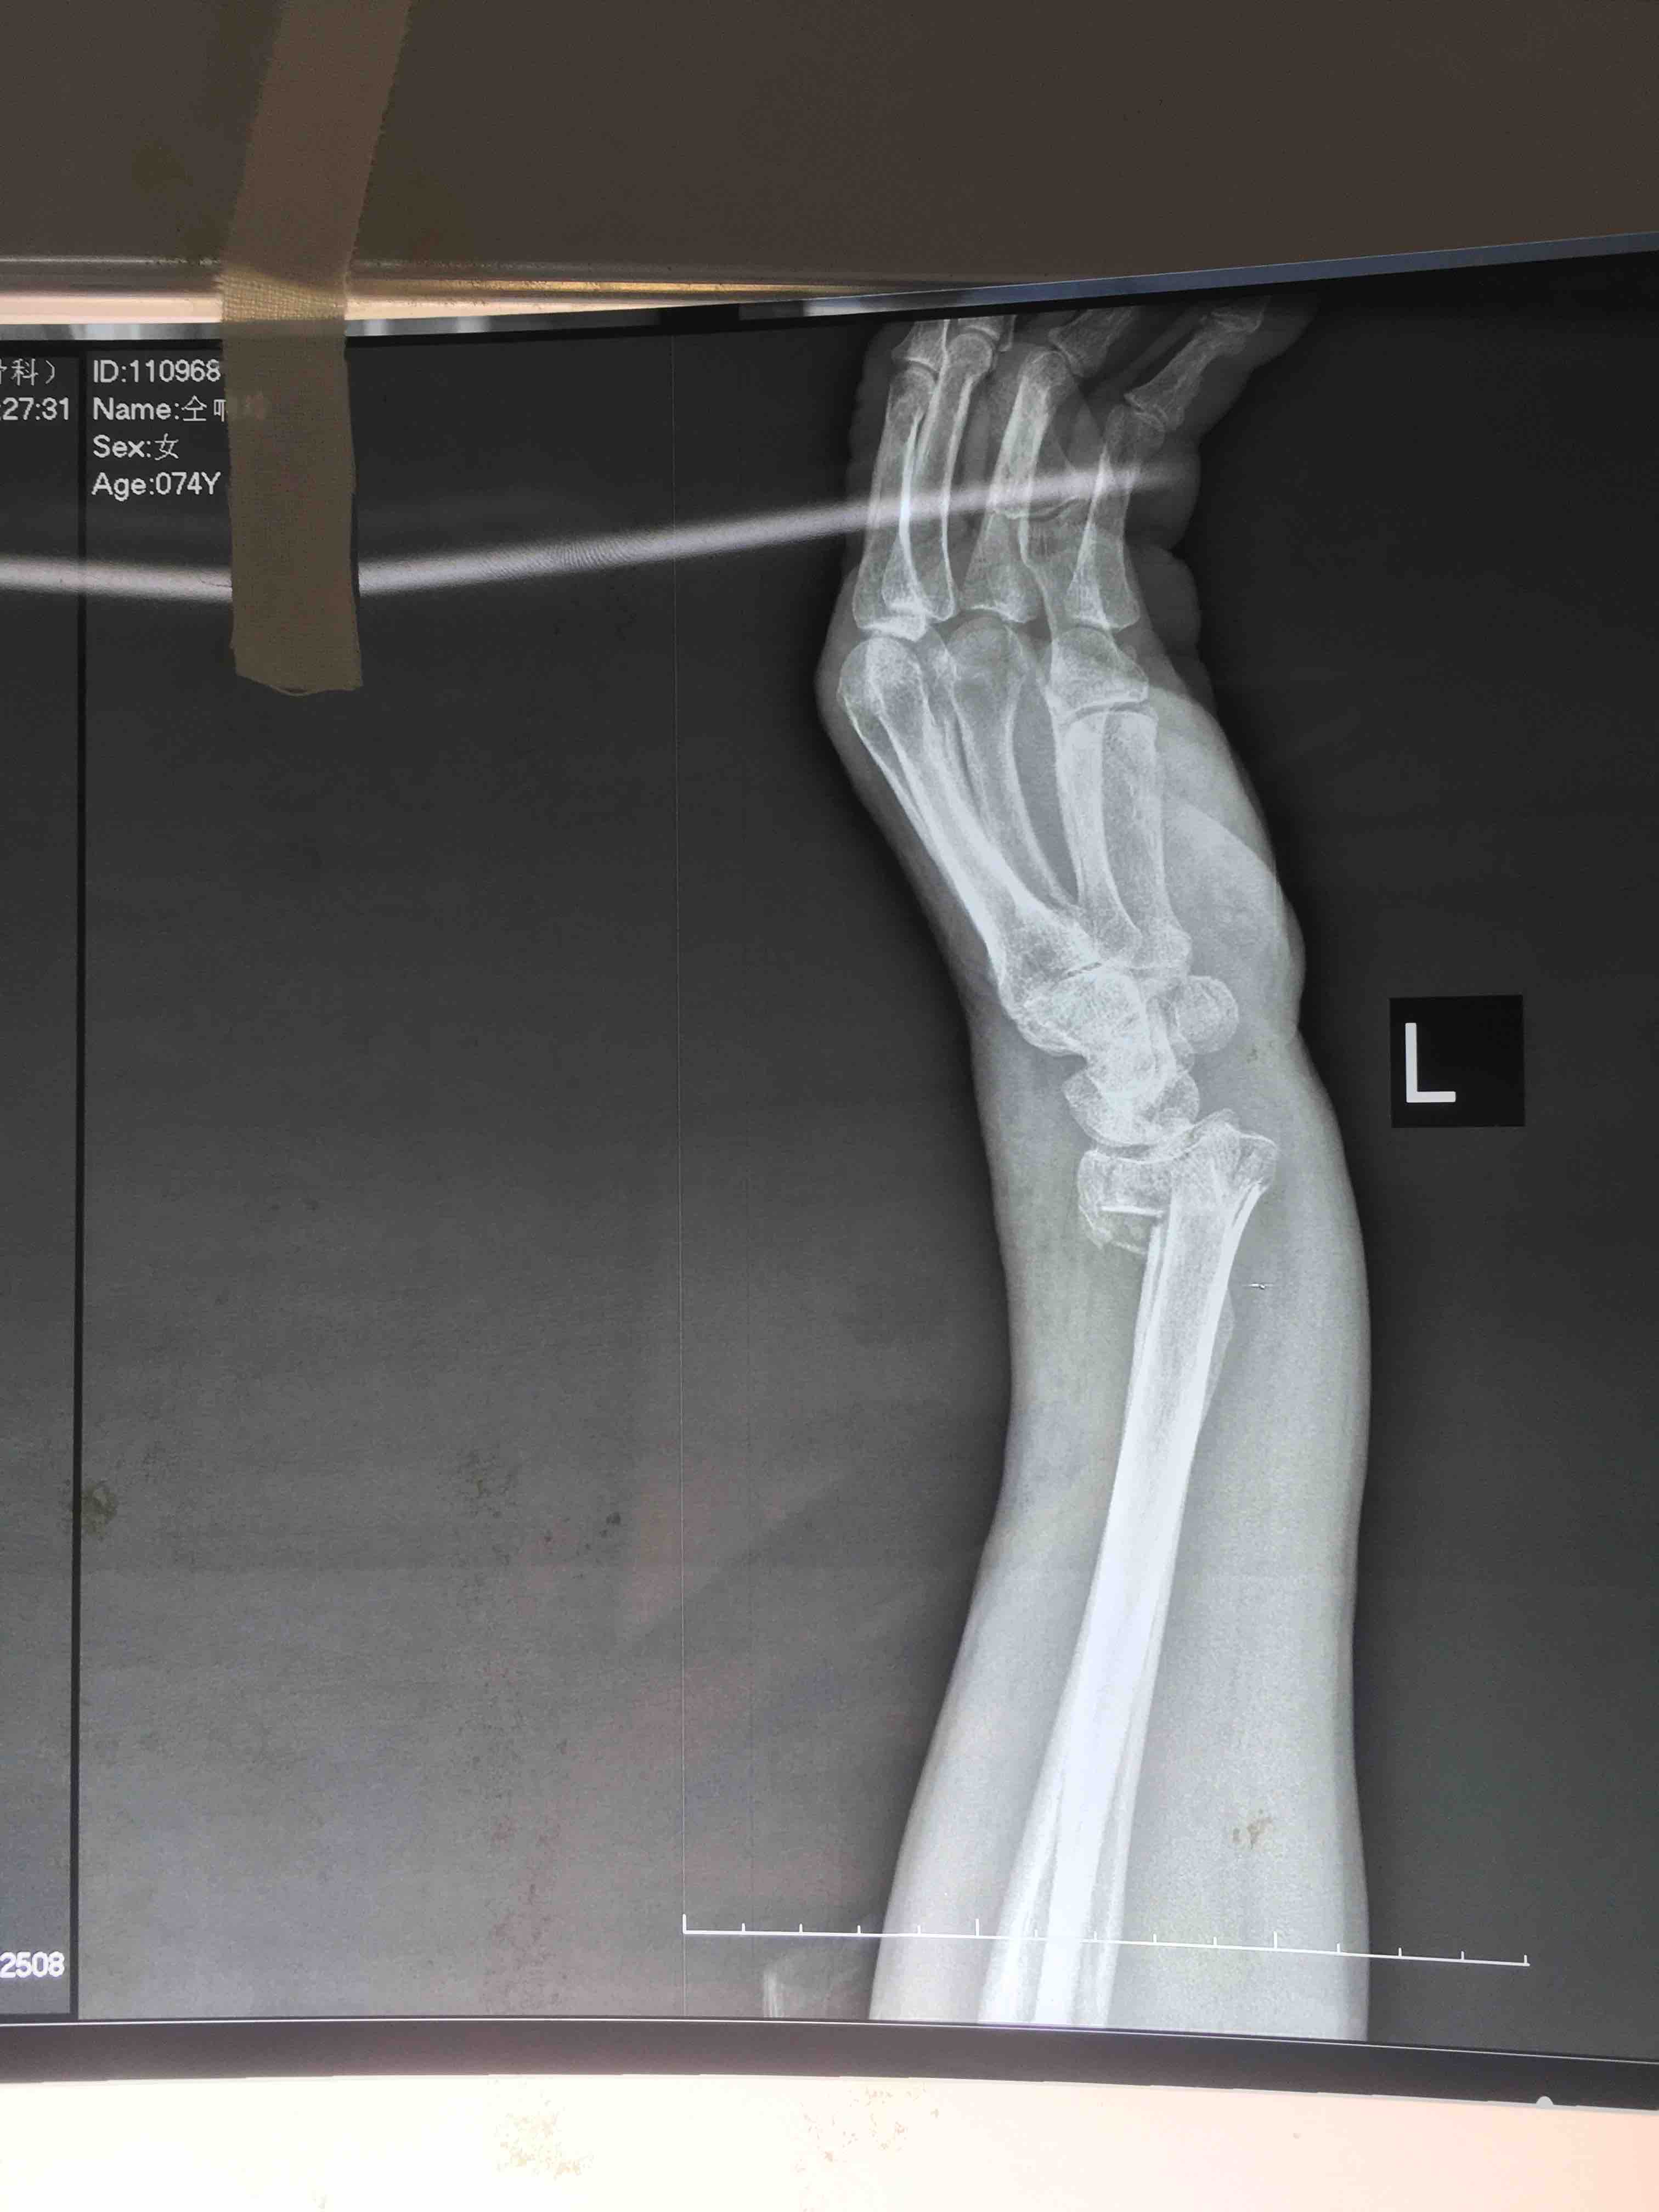

打开应用老年患者colles骨折(切复内固定术)

患者:女/七十四岁

摔伤后左肿痛,活动受限1小时入院。

左腕部肿胀明显,畸形,局部压痛及纵向叩痛阳性,活动受限,末梢血运感觉正常。

诊断 治疗

在臂丛麻醉下行切复内固定术,术后抗炎对症处理。